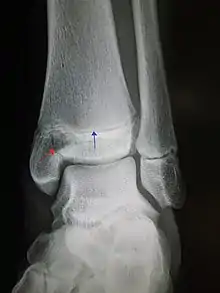

An X-ray of the left ankle showing a Salter–Harris type III fracture of medial malleolus. Red arrow demonstrates fracture line while the blue arrow marks the growth plate.

• Type III – A fracture through growth plate and epiphysis, sparing the metaphysis:[9] 8% incidence